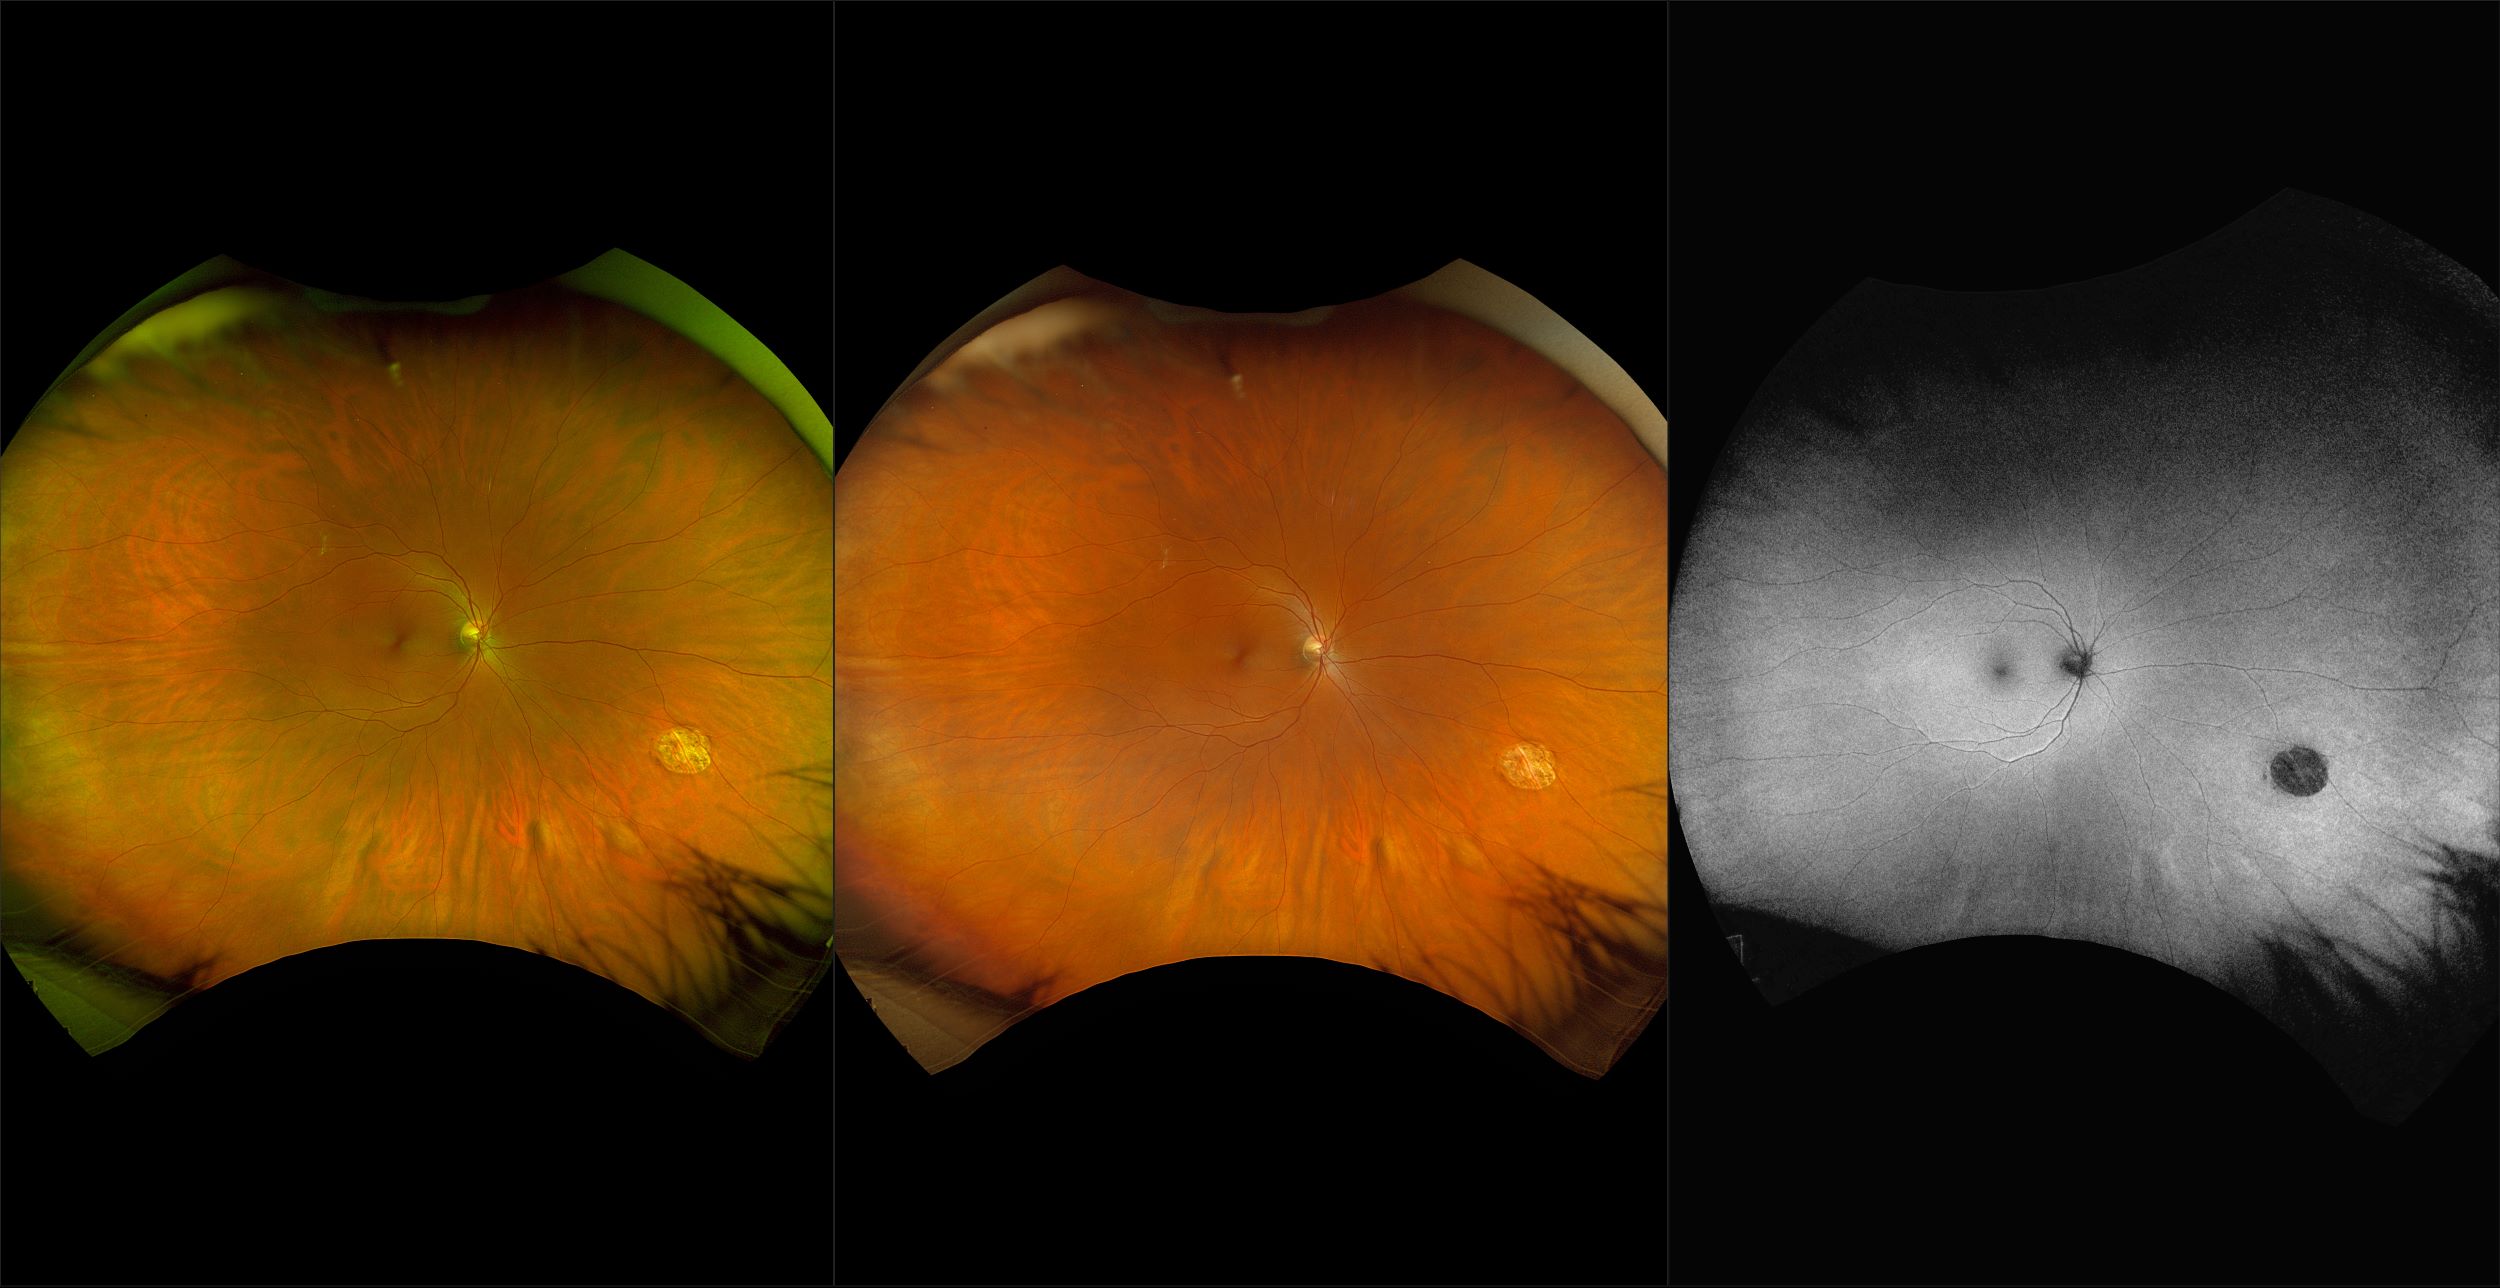

California - AMD, RG, AF

Age-related macular degeneration is found in two forms 1. Dry early form. 2. Wet (serous leakage or whole blood). Early dry form typically has drusen (usually around 63u) and RPE degeneration and only needs periodic follow-ups, intermediate dry form has large drusen (>125u) and RPE degeneration and proliferation which requires examinations every 3 to 6 months depending on the severity of the presentation.